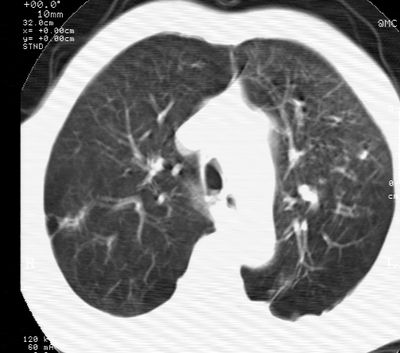

标题: CT24000:M65,胸痛,胸闷月余,既往慢支,肺气肿,肺心病 [打印本页]

标题: CT24000:M65,胸痛,胸闷月余,既往慢支,肺气肿,肺心病

左肺门肿块,相应支气管闭塞,左肺上叶、舌叶大片及散在高密度影,部分呈不张改变,两肺纹粗乱,左侧胸腔积液。考虑左侧中央型肺癌伴阻塞性改变。

左肺门见巨大软组织肿块影,直径约--,境界清,左上肺叶支气管变窄,左上肺舌叶见大片状密实影,余肺纹理增多、紊乱、纤细、部分网格状,两肺透亮度增高,纵隔内见增大多发淋巴结影,心影略左偏,左侧少量胸腔积液。

左侧中央型肺癌伴左上肺舌叶不张、纵隔淋巴结转移,左侧少量胸腔积液。